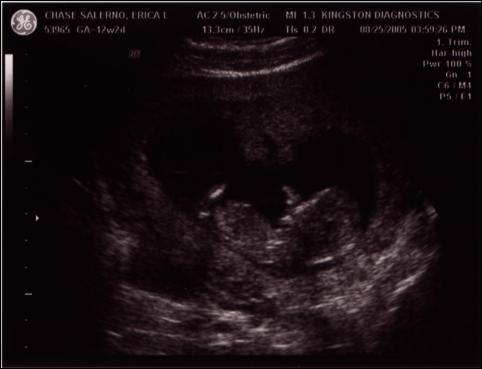

After having researched the potential effects of ultrasounds on fetuses, we decided that we would not get any routine ultrasounds this time around with the pregnancy. So, of course, we ended up having to get one after all, after some health questions came up last week.

We were thrilled to learn that everything is fine – the heartbeat was a healthy 170 beats per minute, the measurements were lined up exactly with the baby’s age (12.5 weeks on 8/24), and we discovered that we have either a thumb-sucker or a nose-picker, depending on what you can make out from the pictures. When Mike and Declan came in to see the images, the baby actually seemed to give them a little wave, and Declan waved back. Seeing the pictures seems to have made it more real for Declan that there’s an actual “baby” in there.

Here are two of the images we got that day – enjoy the world’s first look at Baby #2!